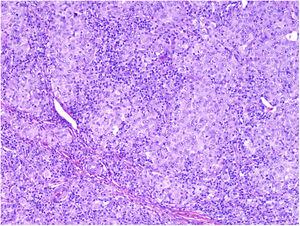

NeurotropismoSe define como la presencia de células de melanoma colindantes con las vainas nerviosas de una forma circunferencial (invasión perineural) (fig. 3) o bien en el interior del nervio (invasión intraneural) (fig. 4). Se suele observar con mayor frecuencia en la periferia del tumor. La presencia de atrapamiento del nervio por el crecimiento tumoral no debe ser considerada como neurotropismo. Está asociado frecuentemente al melanoma desmoplásico. A veces se extiende más allá de los límites del tumor primario, lo que se asocia a una mayor posibilidad de recidiva local36. Se considera actualmente también neurotropismo la diferenciación neural presente en melanomas, generalmente desmoplásicos (fig. 5)10.